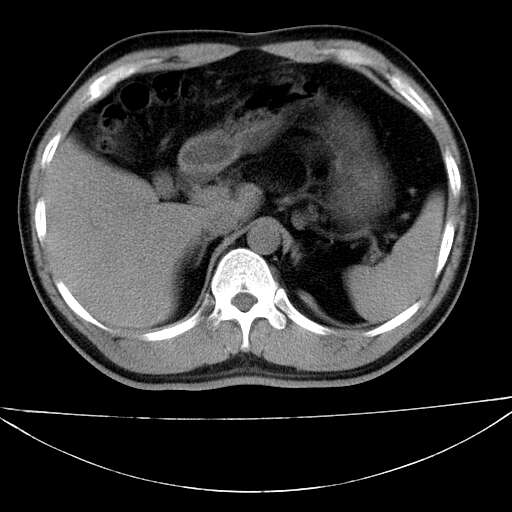

标题: CT21921:腹膜后腔肿物。患者男39Y。体检。增强扫描时间欠准 [打印本页]

标题: CT21921:腹膜后腔肿物。患者男39Y。体检。增强扫描时间欠准

2、左下膈肌脚外缘结节状病变,与胸膜交界面呈锐角,胸膜下脂肪线可见,定位于肺内,考虑支气管囊肿或肺隔离征可能性大。

1)考虑左肺下叶后基底段(或左下胸后壁胸膜)软组织团块,性质待定;建议行进一步检查。2)左肾结石。

左膈肌连续性中断,左侧膈疝可能性大.

左膈肌角后腹膜腔见肿物影,其内见脂肪密度灶及软组织密度灶,强化不明显。病灶大部在后腹膜内。考虑异位嗜铬细胞瘤或脂肪肉瘤、畸胎瘤

左膈肌连续性中断,左侧膈疝可能性大

左下肺隔离症,可见从胸主动脉发出异常血管供应